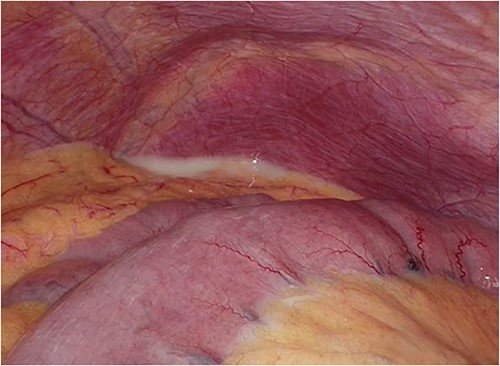

Laparoscopic surgery was initiated. Initial laparoscopic examination revealed an edematous small intestine with mild congestion and milky ascites (Fig. 2). The triglyceride level in the ascitic fluid was 670 mg/dL. Although we attempted to release the torsion laparoscopically, it was difficult to manipulate with forceps because of the edematous intestinal tract and mesentery; therefore, the patient was transferred to laparotomy. The entire small bowel was observed to be twisted 360° counterclockwise, and was therefore manually untwisted (Fig. 3). The duodenum was not fixed to the retroperitoneum as a horizontal leg, but was free from the retroperitoneum on the right side of the vertebral body. We examined the intestinal tract after untwisting and found no evidence of ischemia or necrosis. However, because a small palm-sized diverticulum was observed on the mesenteric side of the upper jejunum, partial resection of the small bowel, including the diverticulum area, was performed, considering the influence of secondary SBV (Fig. 4). The patient had a good postoperative course, but developed angina during hospitalization and was transferred to the cardiology department on postoperative Day 23.

Intraoperative photograph showing a small palm-sized diverticulum on the mesenteric side of the upper jejunum.